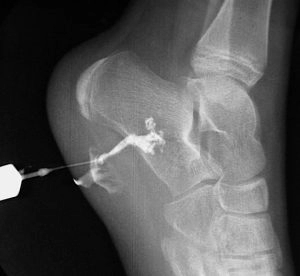

ФистулографияФистулографией называют такой способ рентген-исследований, при котором изучаются свищи независимо от их локализации. Этот метод необходим для того, чтобы определить особенности лечения, составить дальнейший план лечебных мероприятий. При таком способе предполагается введение в свищ специального контрастного вещества. После этого выполняется рентгеноскопия образования.

Для исследования используют один из двух вариантов контрастного вещества. Это масляный (либо спиртовой) раствор йода и такой же раствор сернокислого бария. Конкретное решение выбирается по ситуации. Например, барий хорошо показал себя при работе с очень широкими свищами для определения стадии патологии.

Также показания к фистулографии включают остеомиелит – поражение костных тканей. Причем процедура удобна тем, что она позволяет понять, в чем причина конкретного свища, например, абсцесс или нахождение в тканях инородного тела. Это помогает точнее поставить диагноз и максимально эффективно назначить лечение.

Перед процедурой выясняется общее состояние пациента, а также его реакция на контрастное вещество. Если аллергии нет, проводится дополнительная подготовка к фистулографии: рентгенограммы в перпендикулярных проекциях, извлечение содержимого из свища и его промывание. Затем вводится контрастное вещество и начинается исследование. Нередко эту процедуру проводят и во время самой операции.